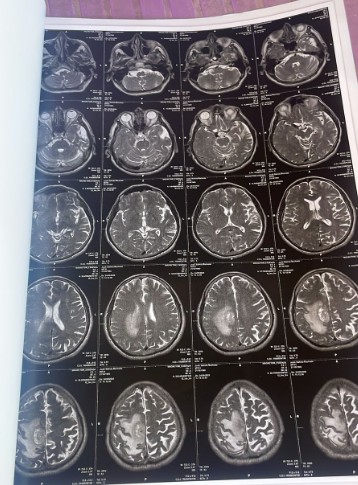

Segundo relatos de familiares, João Batista foi diagnosticado com câncer na cabeça e apresenta quadro considerado grave. O paciente estaria com o cérebro bastante inchado e, conforme os parentes, o estado de saúde piora a cada dia.